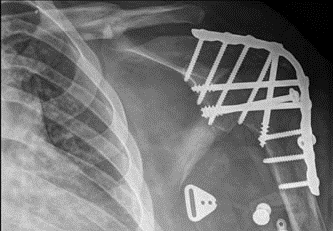

A glenohumeral arthrodesis would be most beneficial to a patient with a flail shoulder but intact elbow and hand function. The goal is to position the shoulder so that the hand can reach the patient's mouth for feeding and groin for hygiene. Learn more: https://anchor.fm/orthobullets/episodes/Shoulder--ElbowShoulder-Arthrodesis-eaihtj/a-a1cv268 …pic.twitter.com/8HI0Vy6Yhi